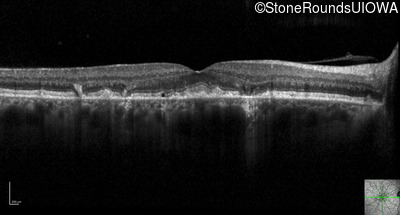

Optical Coherence Tomography - Right - 20/20 -1 sc

Exemplar / OCT Stack